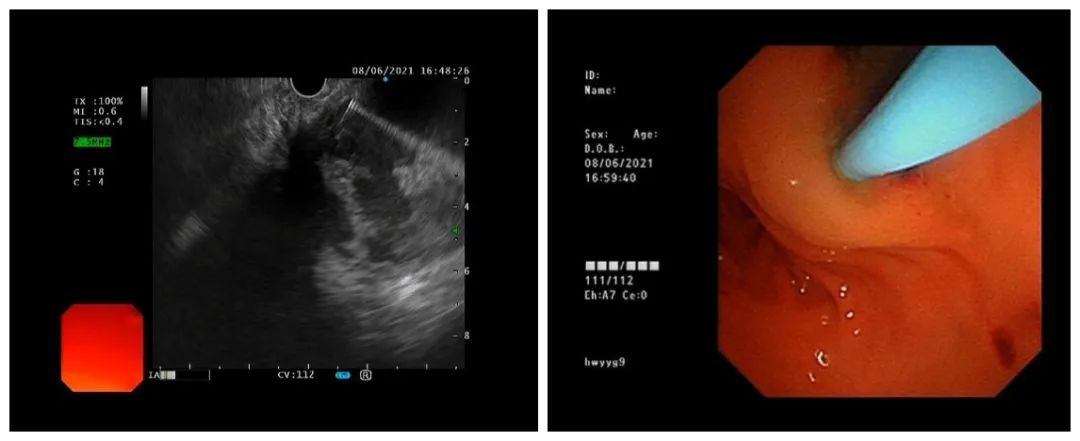

CT显示巨大胰腺假性囊肿,压迫胃肠道(左图)

超声胃镜显示巨大胰腺假性囊肿(右图)

王东判断,由于急性重症胰腺炎,小熙的胰腺组织大量渗出坏死后形成巨大假性囊肿,腹腔内凭空多了一个足球大小的囊肿,压迫周围的消化道,导致腹胀和呕吐。一般4-6周囊肿没有吸收就需要手术治疗了。

为引流囊肿和解除压迫症状,王东为小熙进行了超声胃镜下胰腺巨大假性囊肿引流术,术中抽出了大量稠厚的咖啡色坏死液体。

针对小熙的情况,常规方法即放置支架无法充分引流稠厚的囊液,加之囊肿较大,其底部引流不好的话,易继发感染。因此,为了引流充分和冲洗囊肿,王东主任在超声内镜引导下,穿刺针避开血管穿刺进入囊肿,置入导丝,沿导丝置入鼻囊肿引流管。20分钟左右,手术顺利结束。